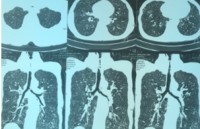

| Cứu sống bệnh nhân suy hô hấp do hẹp khí quản Bệnh viện Phổi Trung ương vừa tiến hành nội soi phế quản ống cứng đặt stent cứu sống bệnh nhân bị suy hô hấp cấp ... |